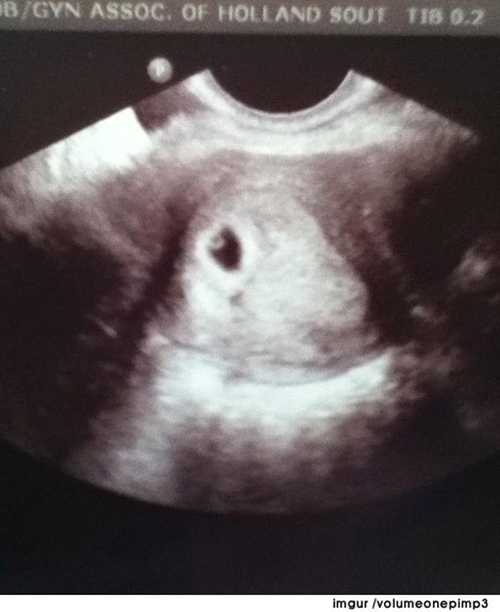

토끼 착시 초음파 사진, 아기 맞아?

[엑스포츠뉴스=대중문화부 방정훈 기자] '토끼 착시 초음파 사진'이라는 게시물이 화제다.

최근 한 온라인 커뮤니티에는 한 아기의 초음파 사진이 공개됐다.

사진 속에는 토끼라고 착각할 만한 모습의 아기의 모습이 담겨 있다.

특히, 눈을 비롯한 얼굴 생김새가 토끼와 상당히 흡사해 보는 이들의 놀라움을 자아내고 있다.

[사진 = 토끼 착시 초음파 사진 ⓒ 온라인 커뮤니티]